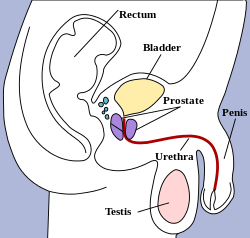

The bladder is a hollow muscular organ situated at the base of the pelvis. Urine collects in the bladder from the two ureters, which open into the bladder at its back and connect to the kidneys. Urine leaves the bladder via the urethra, a single muscular tube which ends in the urethral orifice. Anatomically, the bladder is divided into a fundus at the top, two ureteric orifices, and an opening for the urethra which surrounds the trigone of the bladder. In men, the prostate gland lies outside the opening for the urethra.

The bladder is situated below the peritoneal cavity near the pelvic floor. In men, it lies in front of the rectum, separated by a space. In women, it lies in front of the uterus.

The human urinary bladder is derived from the urogenital sinus, and it is initially continuous with the allantois. In males, the base of the bladder lies between the rectum and the pubic symphysis. It is superior to the prostate, and separated from the rectum by the rectovesical excavation. In females, the bladder sits inferior to the uterus and anterior to the vagina; thus, its maximum capacity is lower than in males. It is separated from the uterus by the vesicouterine excavation. In infants and young children, the urinary bladder is in the abdomen even when empty.[9]

Vertical section of bladder, penis, and urethra. The bladder can be seen highlighted in yellow in the illustration.

The bladder can be seen highlighted in yellow in the illustration.